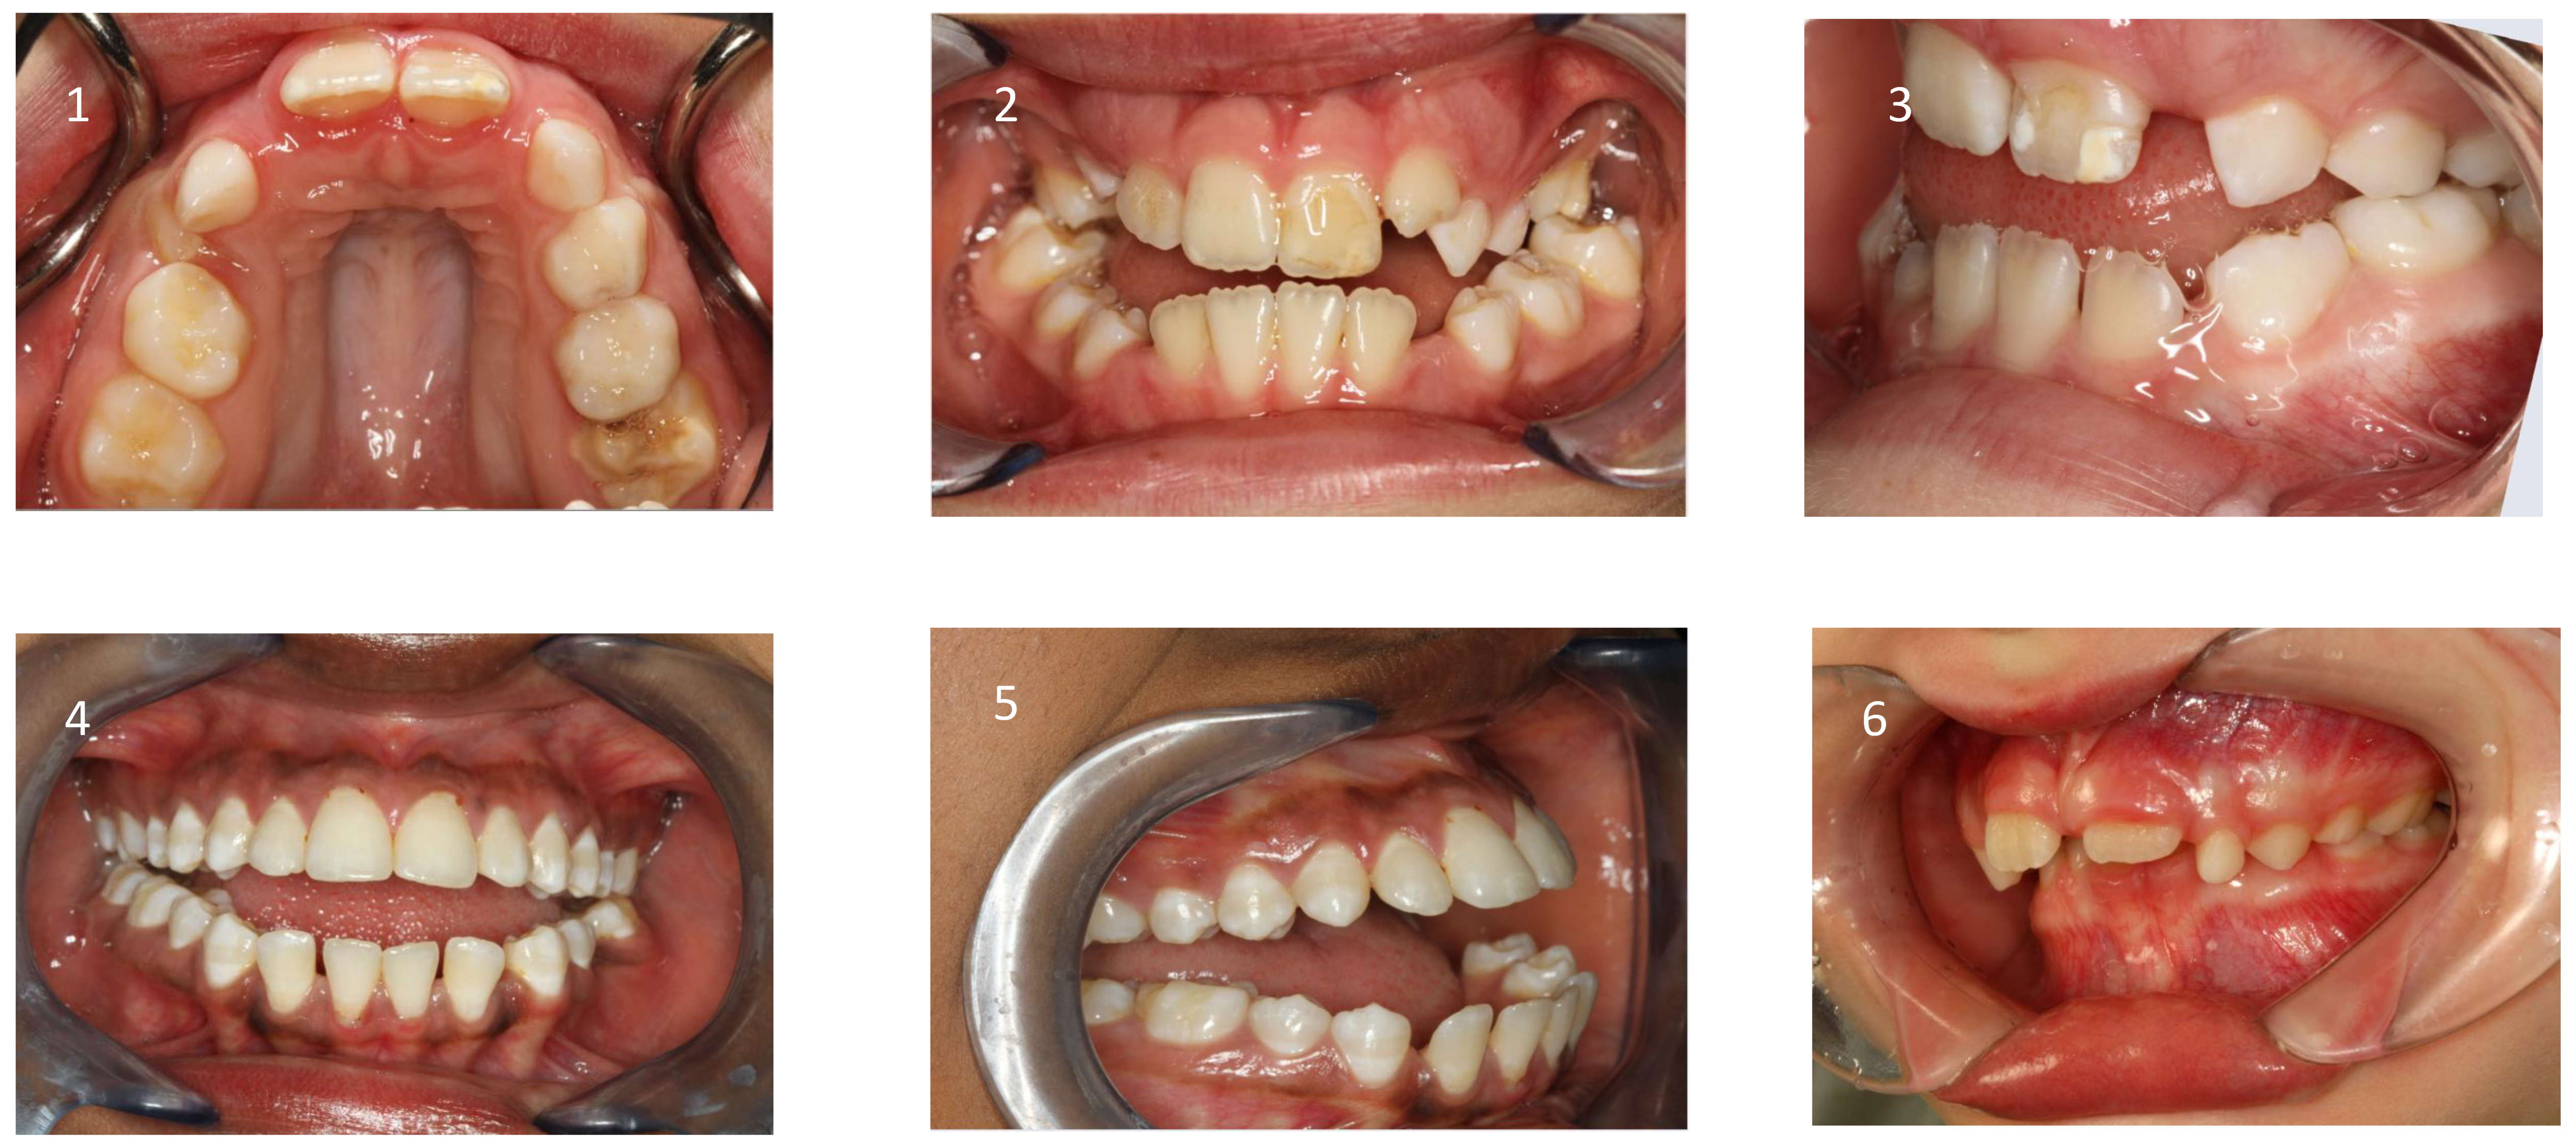

These patients often exhibit “adenoid facies” characteristics and present with dark circles around the eyes, flattened cheekbones, dry lips, an open-mouth posture, a lowered mandibular posture, a low tongue position, labial incompetence, underdeveloped nasal bones, pronounced nasolabial furrows, which collectively complete the typical appearance [49,55,56,57]. They often present a convex profile due to a retrognathic mandible (Figure 4) and an increased mandibular angle. The lower facial third is frequently longer than the average (long-face, dolichofacial morphology) [55]. (Table 2). Additionally, they exhibit an altered head position resulting from hyperextension of the cervical spine and an overall reduction in orofacial muscle tonicity.

5.2. Intraoral Findings

Malocclusion is highly prevalent in children with OSA. They often present posterior crossbites in addition to lateral functional shifts due to a narrow maxilla [70,71,72]. Regarding the palatal vault, it is higher and narrower than in not affected children [73]. This is related to the altered equilibrium between the tongue and cheeks [58]. In addition, an anterior open bite (reduced overbite) and sometimes a deep bite (increased overbite), an increased overjet due to a retrognathic mandible, protruded upper incisors, and crowding in the maxilla and the mandible are constant findings [55,74,75]. (Figure 5 and Table 2)